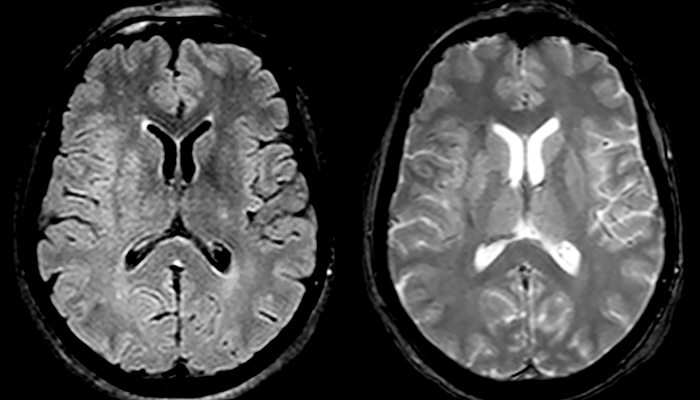

When multiple sclerosis (MS) is suspected, clinicians need a diagnosis early on, so treatment can begin as soon as possible. “A challenge for imaging is that MS lesions in the brain and spine may be very small,” says Dr. Savatovsky. “We need precise imaging to tell exactly where the lesion is, so we need high quality, very high resolution images, preferably in 3D[1]. We need to know if a high T2 signal intensity is suggestive of MS or just aspecific. And we want to visualize active lesions very well.”

“Ingenia 3.0T provides us very good image quality with high SNR, even if we push the resolution. For example, in FLAIR images we may have an isotropic resolution of 0.9 mm. Ingenia allows us to use 3D T1 TSE with BrainView, which has a better sensitivity than 2D spin echo imaging[2] and 3D gradient echo imaging. Ingenia also provides highly reproducible exams, which is important in MS imaging so that follow-up exams at different time points are done the same way.”

For MS imaging in the brain, Dr. Savatovsky uses 3D FLAIR as the basic sequence to visualize the lesions and assess the situation and lesion load. “We count the lesions in each location to determine if the criteria of the disease are fulfilled. We use a T2-weighted sequence because our neurologists are used to it. We compare the lesion load on FLAIR with a 3D T1 post-contrast sequence to help us determine whether lesions are old or new. We typically administer the contrast before the patient enters the machine because it shortens the examination time and allows to visualize active lesions that tend to be more visible after several minutes. When a differential diagnosis is difficult, we add sequences such as susceptibility imaging, because some focal MS lesions have a small vein in the center[3].”